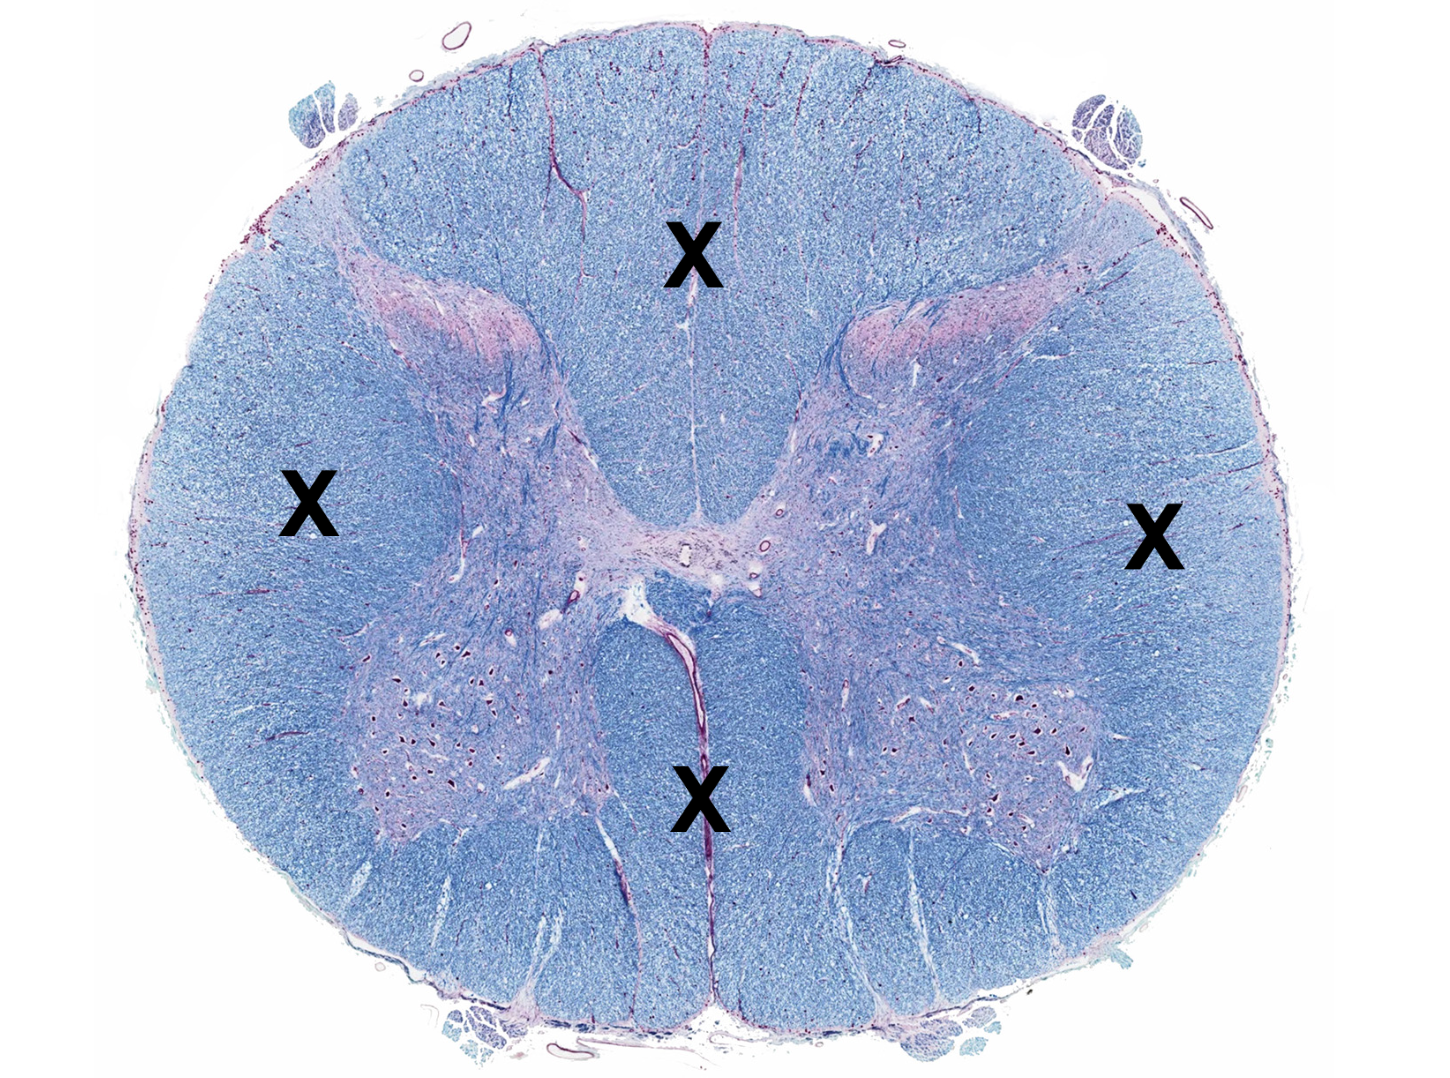

gray matter

posterior horn

anterior horn

lateral horn

gray commissure

central canal

white matter

posterior funiculus

anterior funiculus

lateral funiculus

posterior median sulcus

anterior median fissure